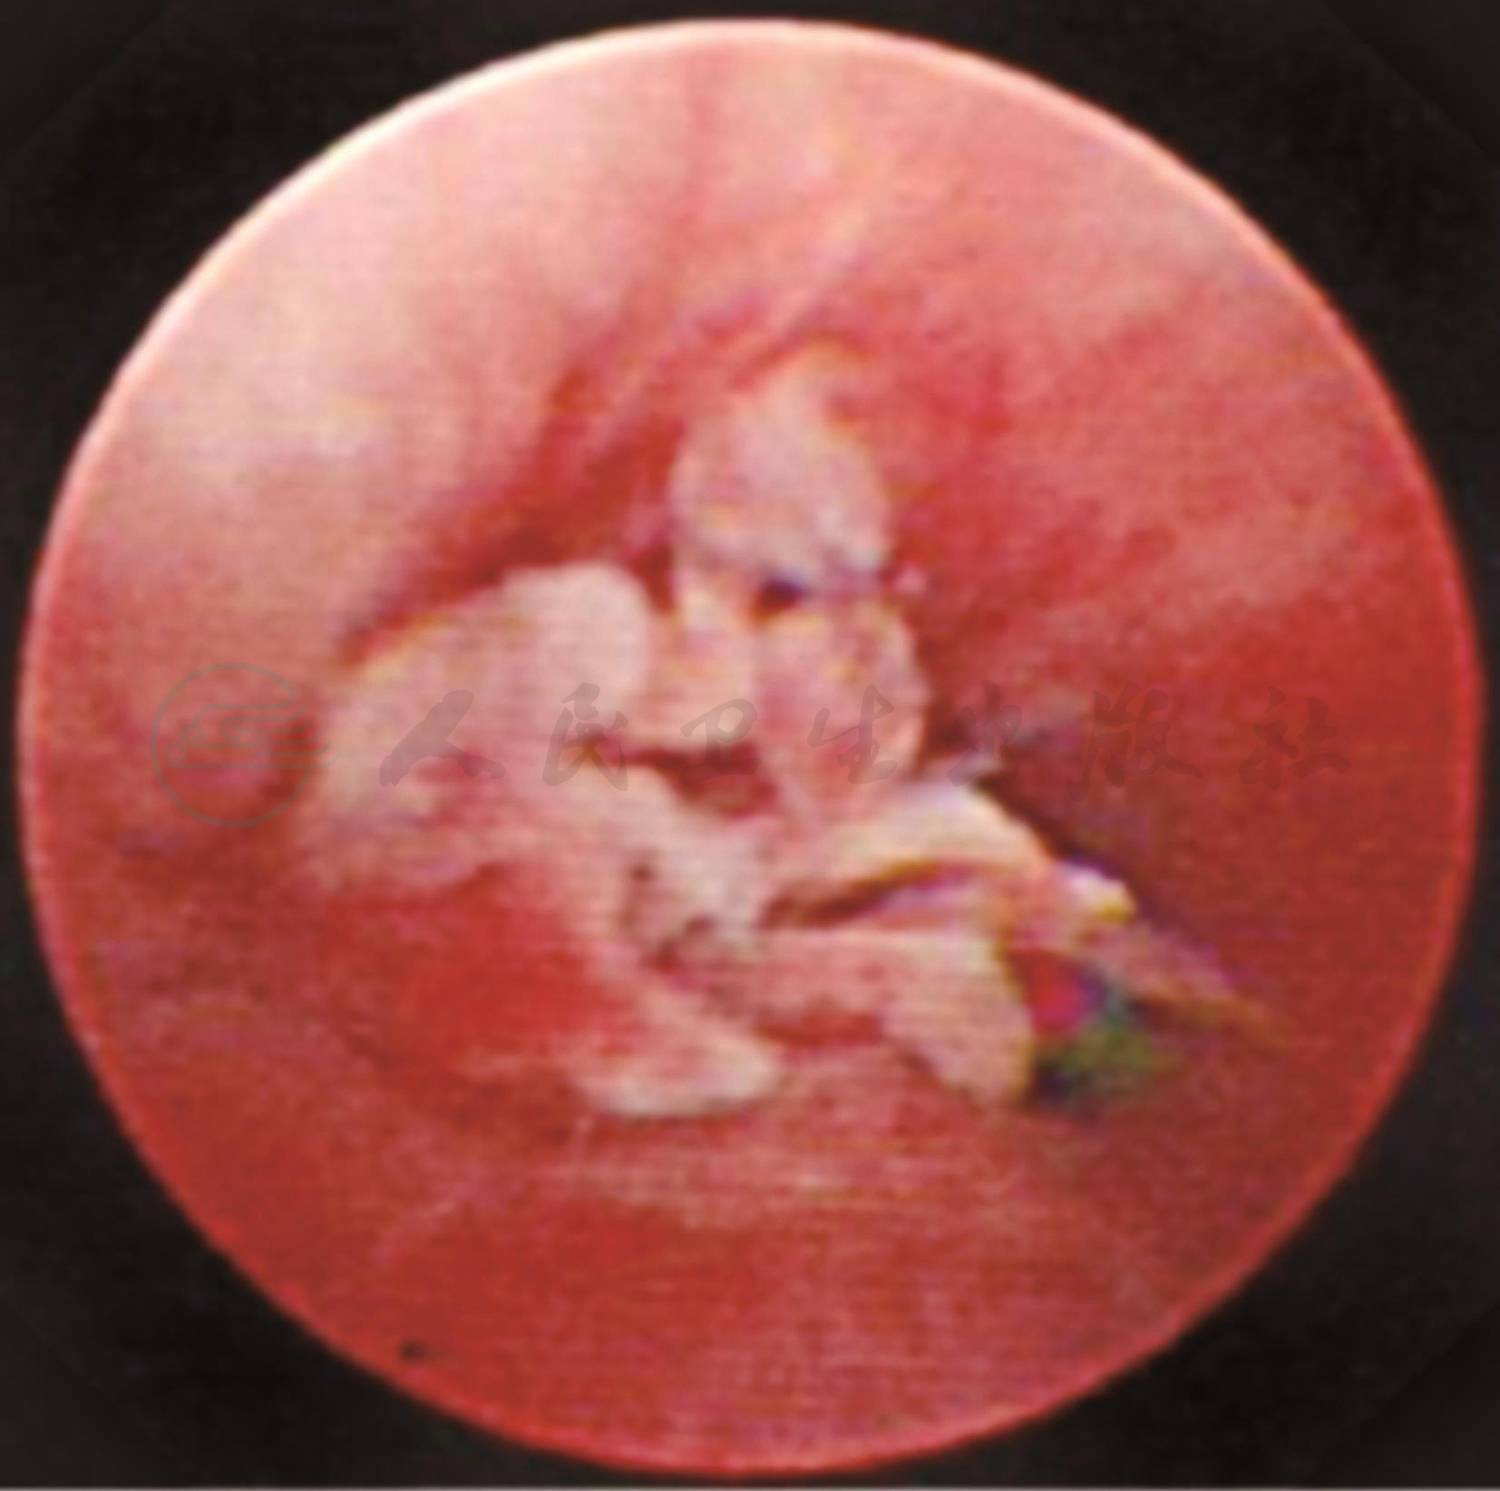

入院第二天行纤维支气管镜检查,镜下可见左肺舌叶(B4、B5)开口处可见一块肿物堵塞大部分管腔(图3),予活检钳钳取部分肿物和留取支气管灌洗液,送病理检查。病理结果回报(图4):(支气管)慢性炎症,局灶见不典型类上皮结节,不除外结核。因此考虑患儿是支气管淋巴结核,结核分枝杆菌突破相邻的支气管内膜,干酪样物进入管腔导致气管腔阻塞。因此增加了抗结核的种类,给予患儿三联抗结核药物(异烟肼、利福平、吡嗪酰胺)口服治疗1个月复查支气管镜。第二次支气管镜下舌叶(B4、B5)开口处可见(图5)黄白色干酪样物质周围被肉芽组织包裹完全堵塞其开口,先用活检钳反复钳取黄白色干酪样物质,并将钳取物分别涂片镜检并送活组织病理检查,考虑常规口服抗结核药物渗透到支气管内膜的浓度小,对局部治疗效果差,因此取了病理后对肉芽组织以及干酪样物进行4次冷冻治疗(每次冷冻时间30~60秒不等)和反复多次钳取,治疗结束后,B5支气管开口得以暴露(图6),其支气管管腔开口通畅,可见正常B5亚段结构,但B4支气管开口仍被肉芽组织覆盖(图7)。分别在第2天后、2周后、1个月后、2.5个月后、6个月后进行5次支气管镜下钳取和冷冻治疗。6个月后第七次支气管镜显示,镜下可见左肺舌叶B5开口通畅,舌叶B4开口形成瘢痕狭窄,2.8mm支气管镜可通过,远端亚段结构正常。复查肺CT可见(图8):左肺上舌叶片状高密度影基本吸收,左肺门肿大淋巴结影较前略减小。

图4 第一次支气管镜黏膜活检病理结果